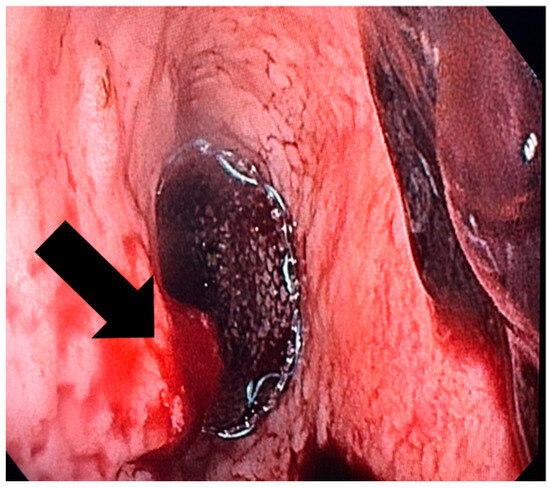

Figure 2. The endoscopic appearance of an eso-jejunal anastomotic fistula following surgical resection of a gastric neoplasm, along with the radiological findings after oral contrast administration.

These procedures were performed by interventional endoscopists using an endoscope equipped with a CO2 inflator. During the diagnostic phase, the fistula (Figure 2) was confirmed and characterized through endoscopic visualization and contrast opacification under fluoroscopy. Key aspects assessed included the size of the orifice (<1 cm, 1–2 cm, >2 cm), the condition of the edges (whether necrotic, inflammatory or fibrous), the presence of pus and any drainage. Based on these findings, the therapeutic phase involved placing a covered metallic stent, applying a clip or using a combination of treatments. The specific endoscopic devices used, and the absence of residual leakage after contrast injection at the end of the procedure, were documented.